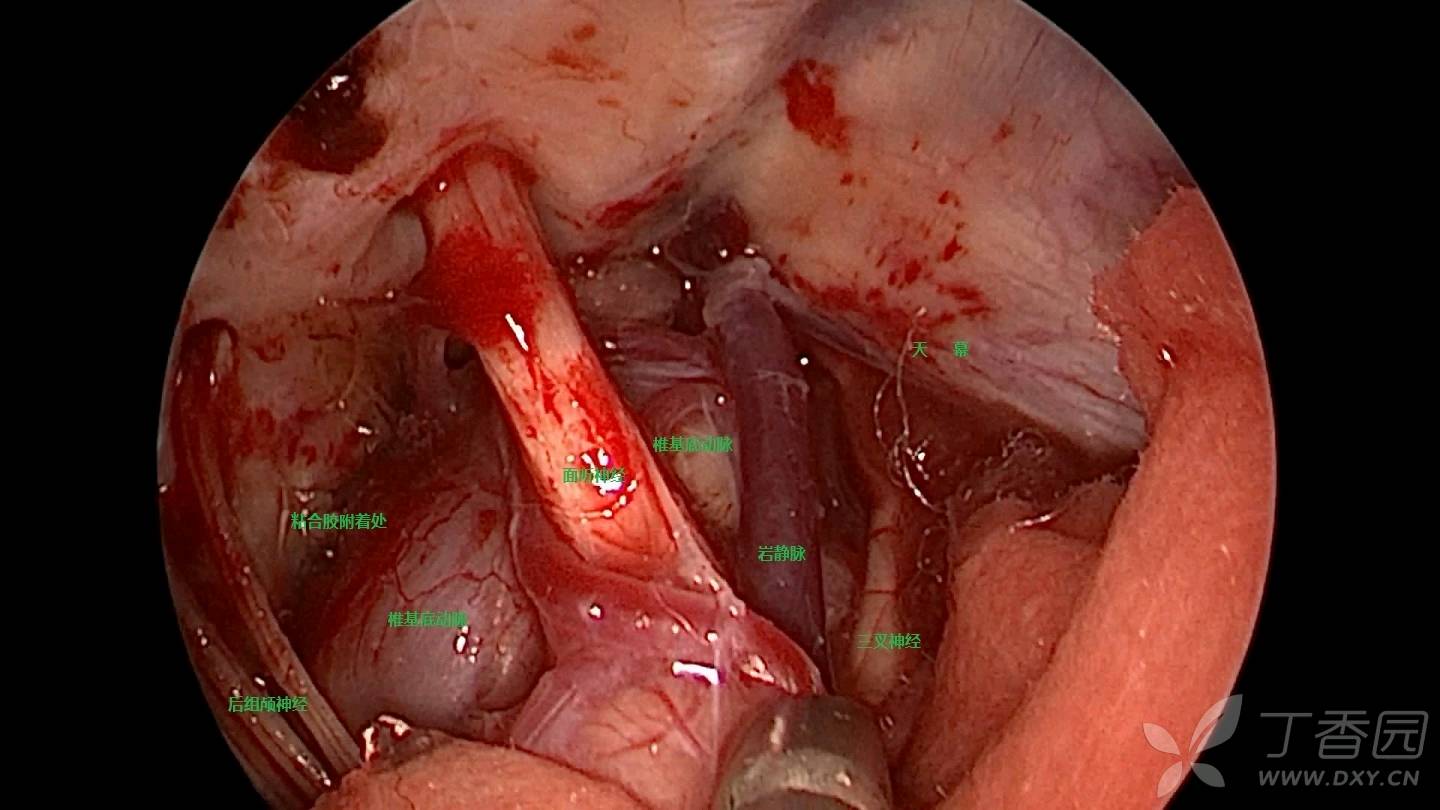

入院完善术前常规检验检查,无明显异常指标及手术禁忌,行左侧三叉神经MVD手术。关键术程如下:手术探查左侧桥小脑角池,见椎基底动脉完全占居桥小脑角区,明显压迫左侧三叉神经脑池段,并将三叉神经顶向天幕(见图7)

图7 椎基底动脉完全占居左侧桥小脑角池,压迫左侧三叉神经脑池段,并将其顶向天幕

推移困难,如勉强垫入Tefflon棉,无法达到减压目的,术者选择于后组颅神经处(舌咽神经)沿三叉神经方向梳理椎基底动脉并垫入Tefflon棉(见图9)

图9 从舌咽神经处沿三叉神经方向梳理椎基底动脉并垫入Tefflon棉

见椎基底动与三叉神经REZ区及近段间出现腔隙,椎基底动脉张力明显降低(见图10)

图10 椎基底动与三叉神经REZ区及近段间出现腔隙

探查见三叉神经中远段仍然受血管压迫,向前下推移虽可离开三叉神经,但因张力极高,直接在神经间垫入Tefflon棉显然不能解除压迫(见图10)。同时因血管巨大,行套索存在困难,遂将血管向下外推向岩骨壁并离开三叉神经,于基底动脉与岩骨壁间注入粘合胶,使椎基底动脉粘附于岩骨壁(见图11、12)

探查见发现椎基底动脉对三叉神经不再构成压迫(见图13)

图13 椎基底动脉粘附于岩骨壁并离开三叉神经

垫入少许Tefflon棉后再行三叉神经旷置,三叉神经下方完全松驰(见图14)

图14 旷置三叉神经

再次探查发现三叉神经上方与天幕粘连明显,予行全程松解(见图14.)。减压完成后行内镜辅助探查,发现三叉神经形态较前恢复,无明显受压(见图15)

图15 三叉神经形态较前恢复,无明显受压